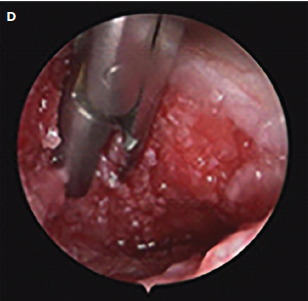

Prospective series evaluates China-Lu endoscopic classification for chronic sinus-tract wounds, examining closure patterns across subtypes to guide prognostication and management.